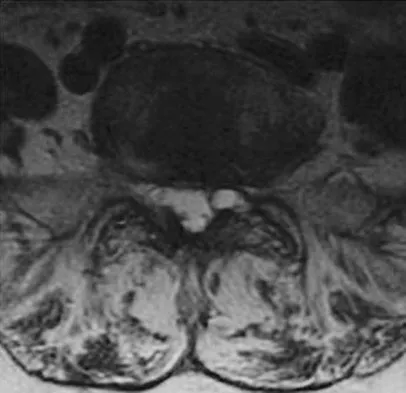

A 13-year-old boy has pain and a firm mass in his left knee. A radiograph and MRI scan are shown in Figures 2a and 2b, and a biopsy specimen is shown in Figure 2c. Based on these findings, what is the most likely diagnosis?

The most likely diagnosis is osteosarcoma. The imaging studies show an aggressive primary tumor of bone, and the histology slide shows a typical chondroblastic osteosarcoma, with osteoid deposited along the surface of bone trabeculae. Ewing's sarcoma histologically consists of small round blue cells. Osteochondroma and periosteal chondroma can occur near the knee but have different radiographic and histologic patterns. Chondrosarcoma rarely occurs in children. Simon M, Springfield D, et al: Osteogenic sarcoma: Surgery for Bone and Soft Tissue Tumors. Philadelphia, PA, Lippincott Raven, 1998, p 267.

Wold LA, et al: Atlas of Orthopaedic Pathology. Philadelphia, PA, WB Saunders, 1990, pp 14-15.